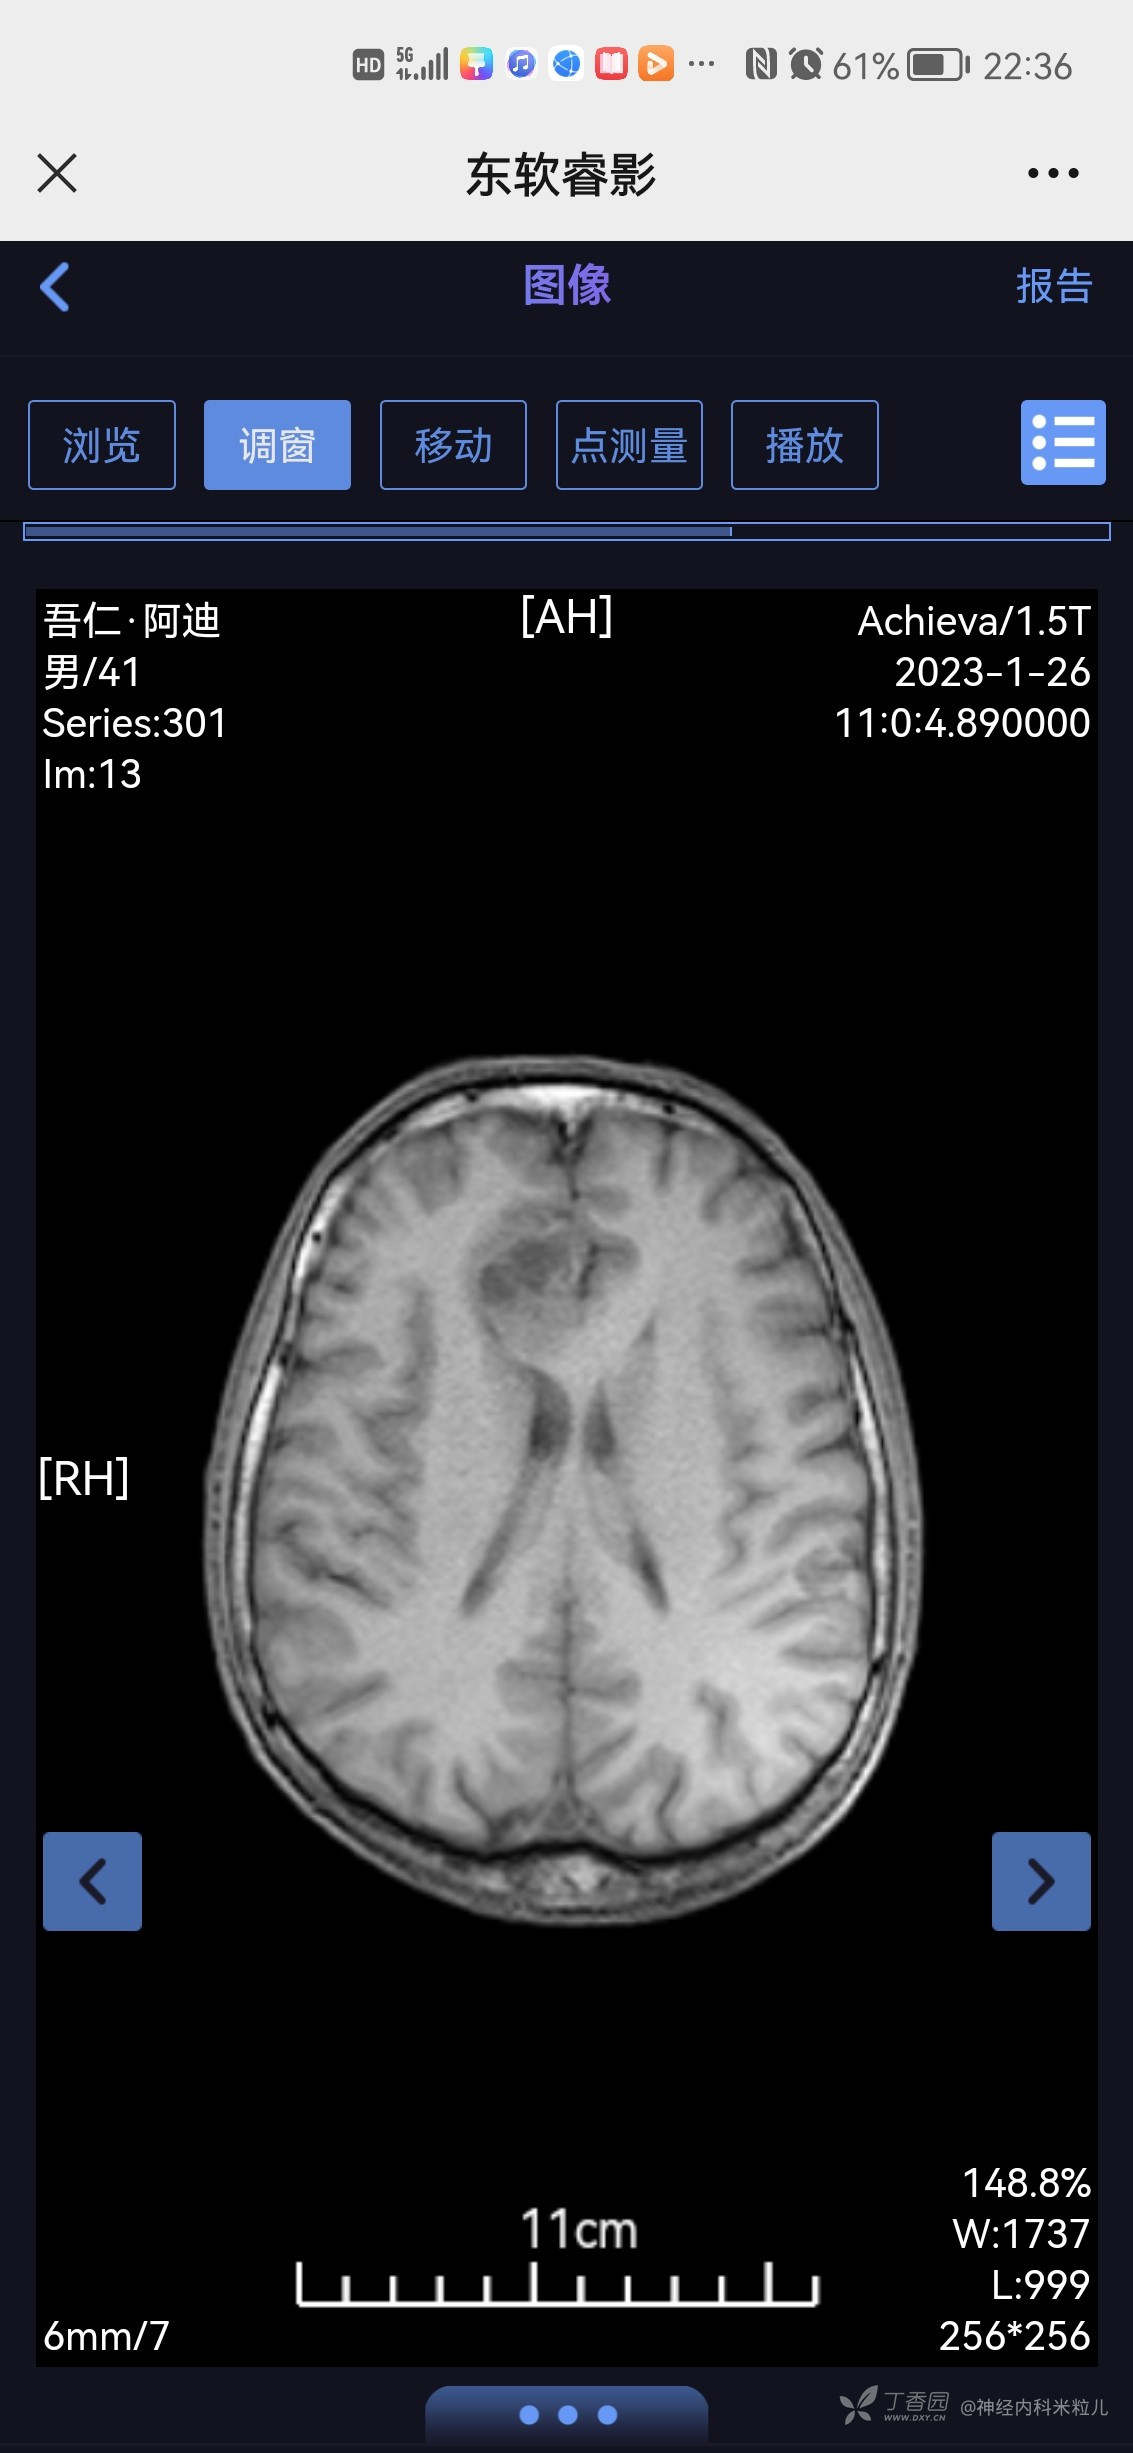

2023年1月18日我院头颅核磁提示:颅内多发异常信号,考虑:感染性病变,建议增强检查。}